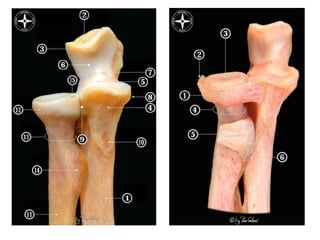

Surgical Anatomy

Osteoarticular

Capsuloligamentous

Muscles

Neurological